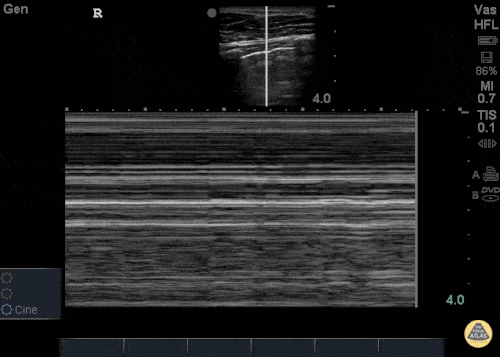

Pneumothorax

Der Pneumothorax spielt v.a. bei Traumapatienten eine wichtige Rolle. So ist der Spannungspneumothorax die häufigste reversible Ursache eines traumatischen Herzkreislaufstillstandes und sollte in der Präklinik entlastet werden (S3-Leitlinie Polytrauma). Sonographisch kann ein Pneumothorax relativ rasch diagnostiziert werden. Die Bewegung der Pleura bei der Atemexkursion lässt sich darstellen („Ameisenlaufen“). Fehlt diese Bewegung, so liegt ein Pneumothorax vor. Im M-Mode lässt sich dies eindrücklich als sogenanntes „Barcode-Zeichen“ darstellen. An der Grenze zwischen anliegender Lunge und Pneumothorax befindet sich der sogenannte Lungenpunkt. Dieser beweist einen Pneumothorax.

Quelle: http://www.thepocusatlas.com/pulmonary CC BY-NC 4.0